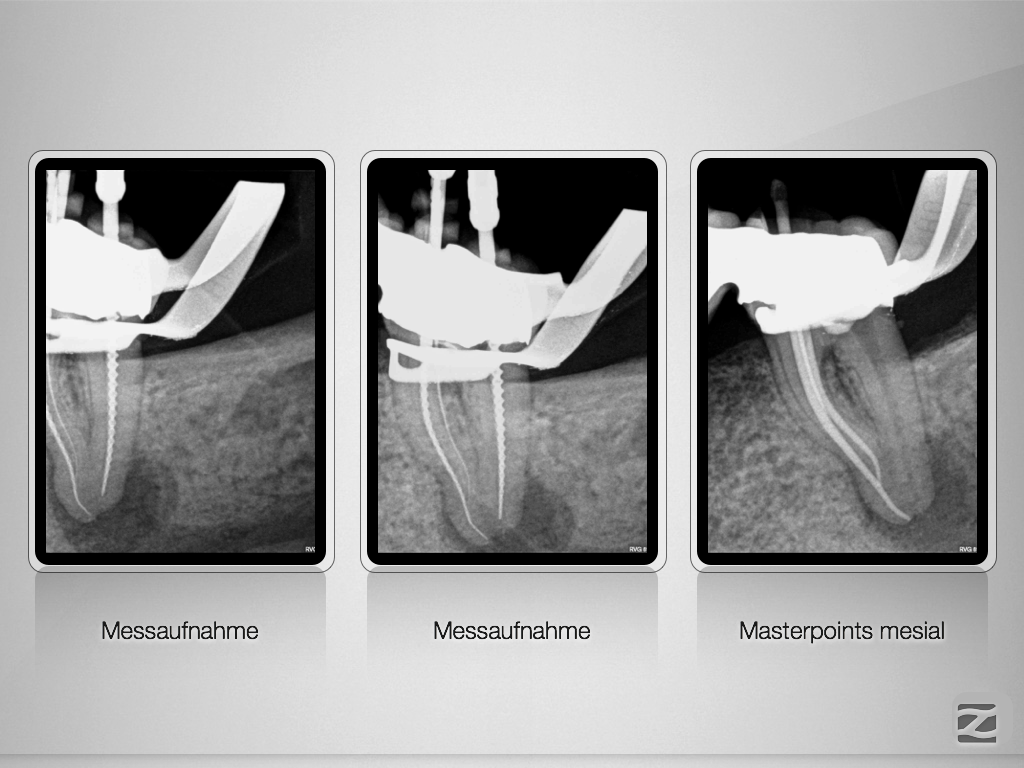

Hyflex Fallbeispiel (2/3)